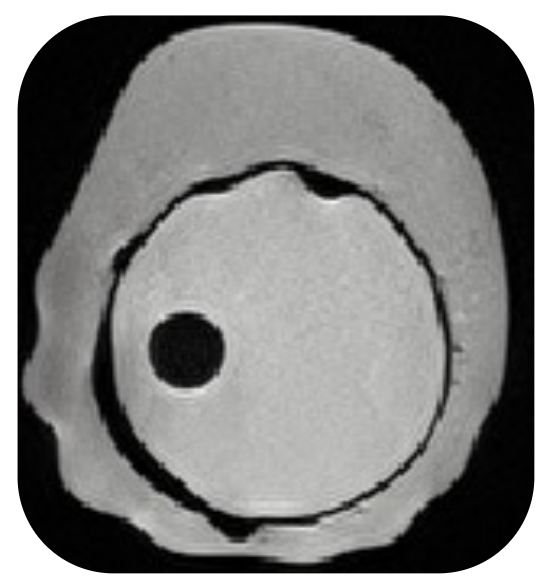

A proof-of-concept artificial palpation for breast cancer detection using tactile sensors.

The red dot marks the current tactile sensor position.

Palpation, the use of touch in medical examination, is almost exclusively performed by humans. We investigate a proof of concept for an artificial palpation method based on self-supervised learning. Our key idea is that an encoder-decoder framework can learn a \textit{representation} from a sequence of tactile measurements that contains all the relevant information about the palpated object. We conjecture that such a representation can be used for downstream tasks such as tactile imaging and change detection. With enough training data, it should capture intricate patterns in the tactile measurements that go beyond a simple map of forces -- the current state of the art. To validate our approach, we both develop a simulation environment and collect a real-world dataset of soft objects and corresponding ground truth images obtained by magnetic resonance imaging (MRI). We collect palpation sequences using a robot equipped with a tactile sensor, and train a model that predicts sensory readings at different positions on the object. We investigate the representation learned in this process, and demonstrate its use in imaging and change detection.